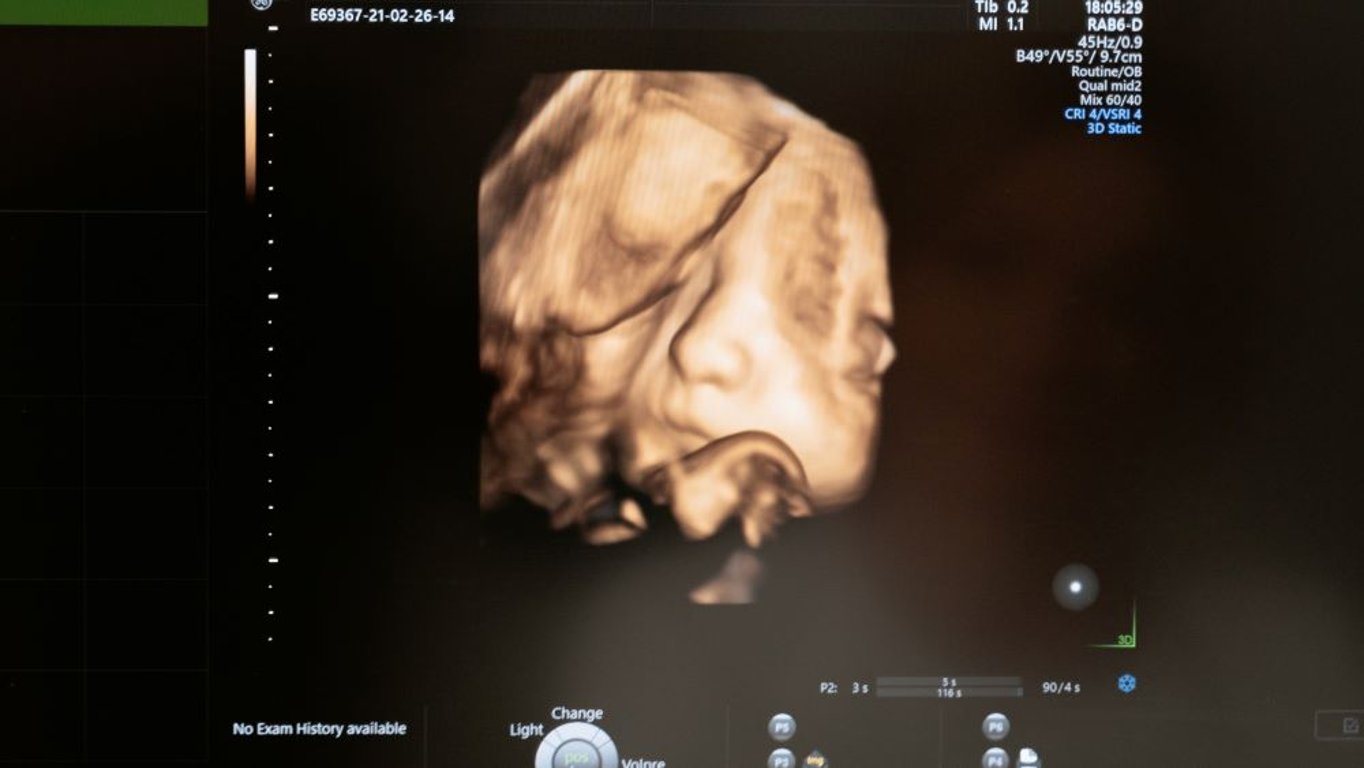

Na ultrazvuku to vypadalo jako obyčejné miminko s vlásky. Skutečnost ale ohromila i zkušené lékaře

Přestože byli nastávající rodiče upozorněni na to, že se jejich miminko narodí s něčím zvláštním, byli při porodu maximálně překvapeni.